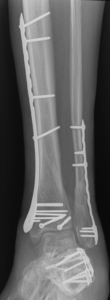

Nonunion and malunion repair related to post-traumatic conditions and/or prior surgery

Acute fracture care of the pelvis and the extremities